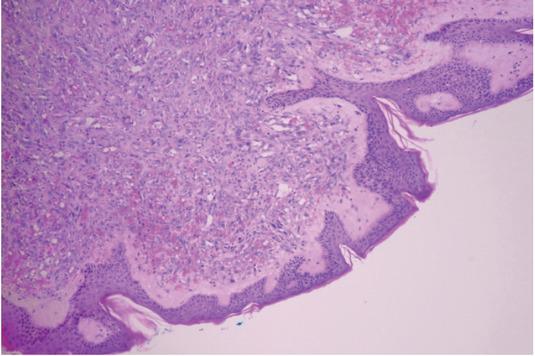

Pathologic hematoxylin and eosin (HE) specimen showing radiotherapy-associated angiosarcoma (RAA) involving dermis.

She had regular follow up and was doing well until the lesion in her right breast was presented in October 2015. First, it was treated as fungal infection with topical ointments and later with corticosteroid ointments. Eight months after the first presentation, fine needle aspiration biopsy was done and suggested a melanocytic lesion, possible melanoma. In June 2016, excision of the lesion was performed and pathological examination revealed RAA, high grade, multinodular, involving dermis and free flap, infiltrating lateral resection margins (Figure 2). Amplification of the MYC oncogene was confirmed using fluorescence in situ hybridization (FISH) method (Figure 3). Patient underwent six cycles of chemotherapy with paclitaxel followed by wide resection of the affected area in January 2017. Pathological examination revealed multifocal residual angiosarcoma in area of 10 cm in diameter, involving skin and subcutaneous tissue with at least 1 cm clear resection margins. Four months after the last operation, in May 2017, she developed second local recurrence with multiple small skin lesion around the scar of the right breast. She received second-line chemotherapy with liposomal doxorubicin with stagnation of the lesions.